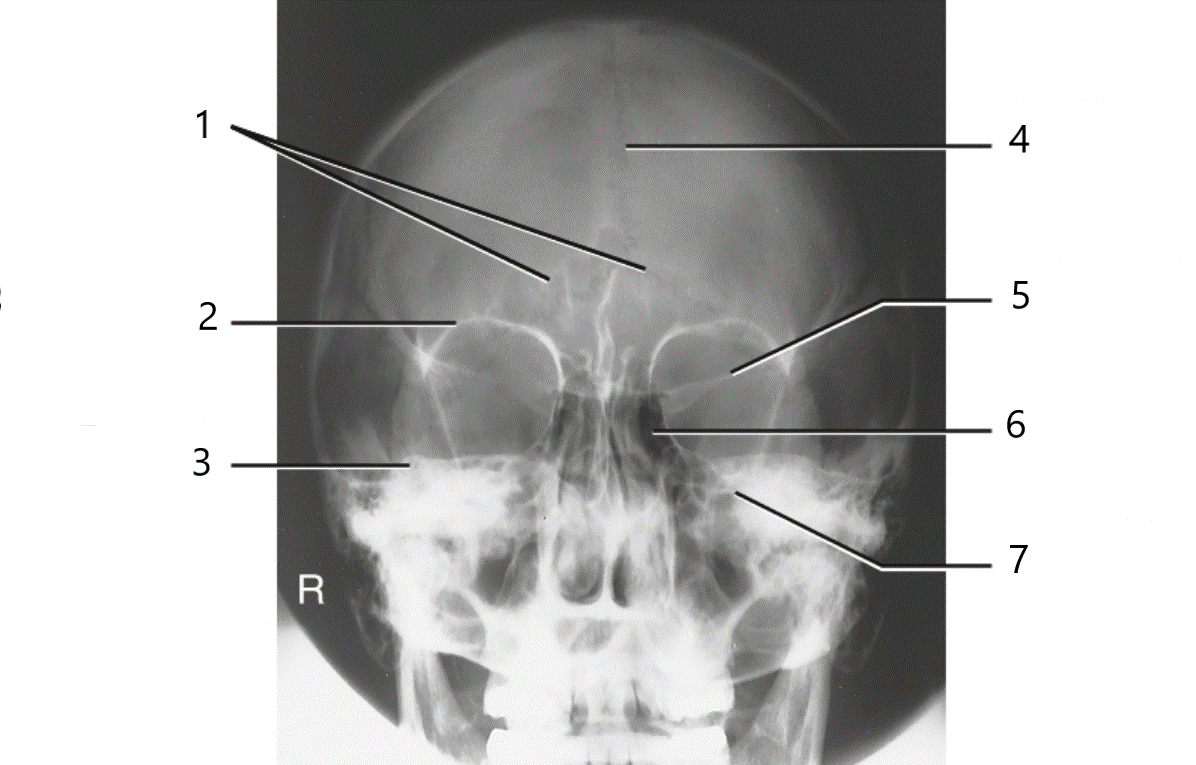

Which sinuses are best demonstrated by the following image?

frontal and ethmoid